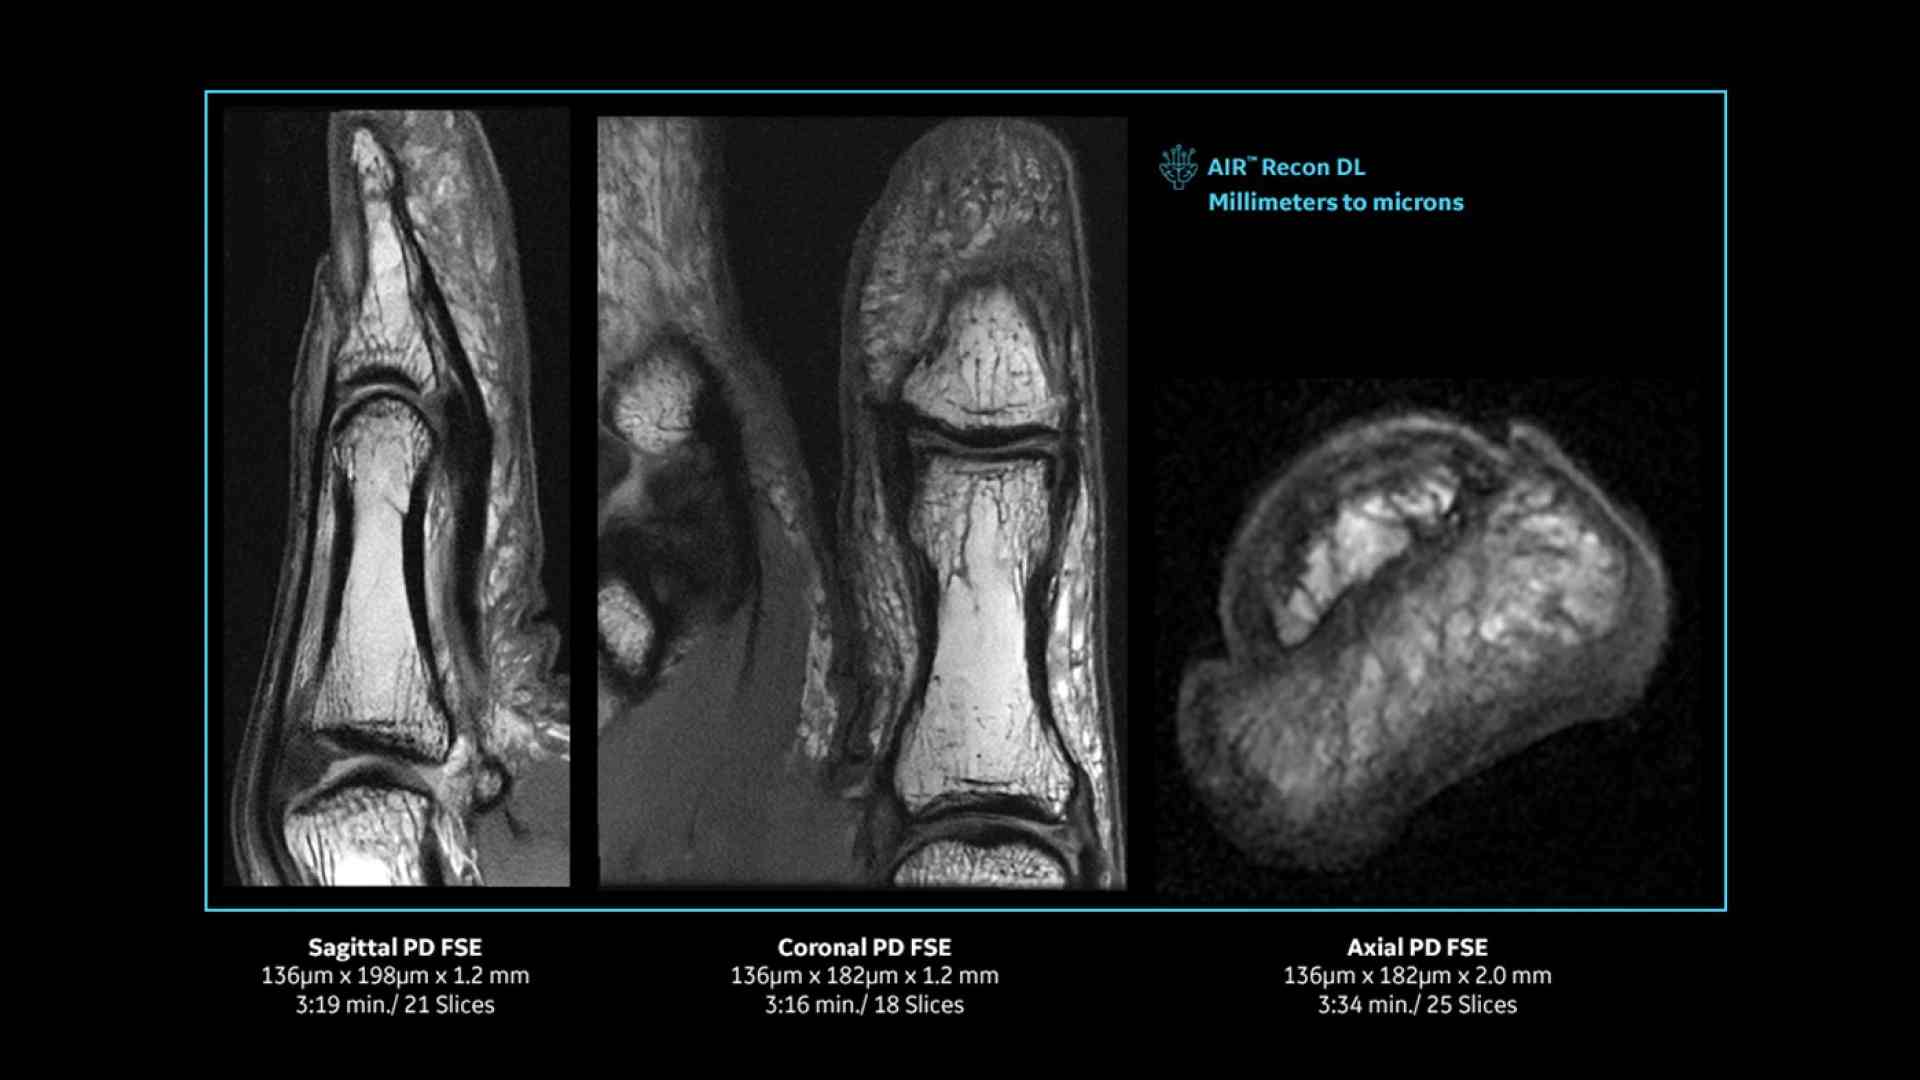

Revolutionary, deep-learning-based reconstruction techniques such as AIR™ Recon DL provide sharper, clearer, and accurate images

Pin-sharp image quality and exceptional speed with AIR™ Recon DL and Sonic™ DL​

Experience pin-sharp precision and remarkable speed with a 3T SIGNA™ Premier MRI scanner, coupled with AIR™ Recon DL and Sonic™ DL.